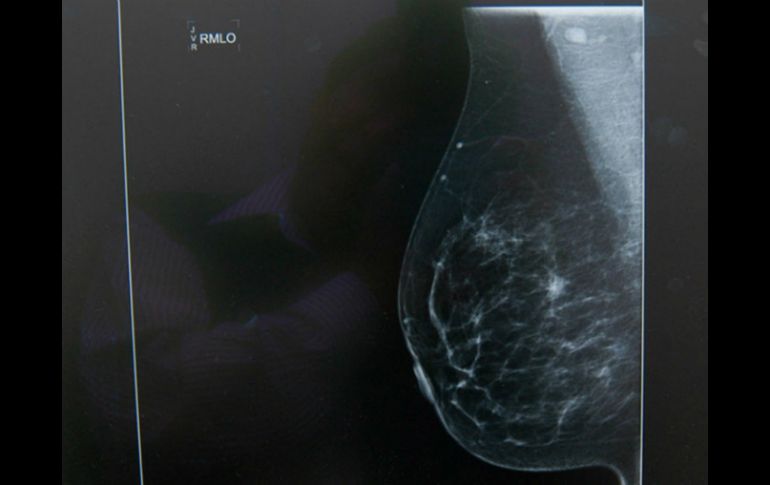

Esta prueba es un pretamizaje  para una detención oportuna, no sustituye a la mastografía. NTX / ARCHIVO

Esta prueba es un pretamizaje para una detección oportuna, sin embargo, no sustituye a la mastografía, solo es un complemento a este examen, precisó.

"La mastografía sigue siendo el tamizaje por excelencia y los resultados son marcados; no obstante, sí podemos hacer una selección de grupos de riesgo para enviar posteriormente a mastografía si tienen una cantidad elevada de micronúcleos en sus células de mucosa bucal", comentó.